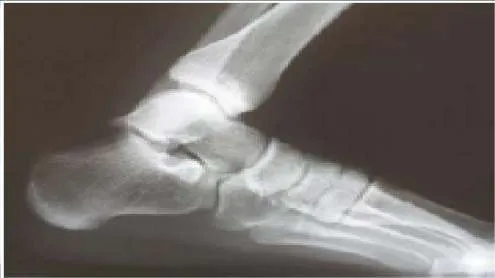

A patient sustained a fracture of the calcaneus 9 months ago. The fracture was treated with non-weight bearing and cast immobilization. The patient experiences constant pain and is unable to work. On examination, he has limited inversion, eversion motion of the foot, and lateral foot pain. Radiographs are presented. The recommended treatment is:

Correct Answer: Subtalar arthrodesis

In the presence of stiffness of the subtalar joint, physical therapy modalities are unlikely to improve the foot function. For the young active worker, an early subtalar arthrodesis is the most reliable procedure to return him to work and an active lifestyle. A triple arthrodesis is contraindicated in the absence of painful transverse tarsal arthritis.